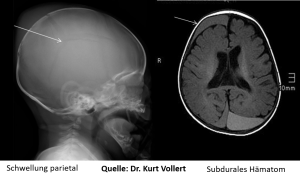

Eine der häufigsten Folgen nach Misshandlung ist das Schütteltrauma, das entsteht, wenn das Kind am Brustkorb gehalten und massiv geschüttelt wird, so dass der Kopf heftigen Schleuderbewegungen ausgesetzt ist. Die Folge sind oft Subduralhämatome, Blutergüsse unter der Hirnhaut, die nur mit bildgebenden Verfahren zu erkennen sind.

Entsprechend den Leitlinien der Gesellschaft für Pädiatrische Radiologie (GPR) werden bei Verdacht auf Misshandlung standardmäßig folgende bildgebende Verfahren durchgeführt: Ein sogenannter Ganzkörperstatus, bestehend aus Röntgenaufnahmen des Schädels in zwei Ebenen, eine Thoraxaufnahme, Beckenübersichtsaufnahme, Aufnahmen der oberen und unteren Extremitäten in einer Ebene und eine Aufnahme der Wirbelsäule seitlich. Dann folgt ergänzend eine Ultraschalluntersuchung des Schädels und des Abdomens. Wenn aufgrund des Alters des Kindes die Hirnstrukturen nicht mehr schallbar sind, kommt die Kernspintomographie zum Einsatz.